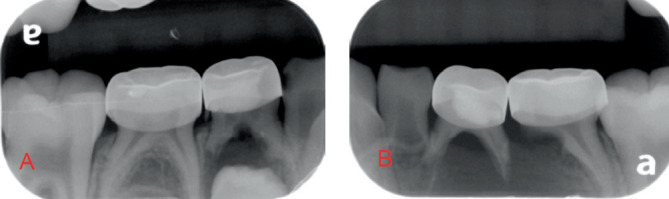

Dentigerous cysts are common odontogenic cysts that can cause significant disruption to normal tooth eruption and jaw development in pediatric patients. Traditional marsupialization techniques rely on tissue-borne appliances, which often lead to discomfort and frequent dislodgement in young patients. This case report presents a novel tooth-borne appliance, the Kang Appliance, as an effective alternative for marsupialization.